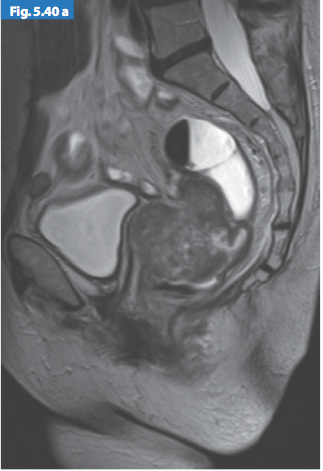

Hình 6. Sự giảm tín hiệu của khối u xâm lấn vào thành sau âm đạo

Hình 7. Khối u giai đoạn T4 trên hình ảnh T2w axial xâm lấn lá phúc mạc và cổ tử cung

Hình 8. Khối u giai đoạn T4 trên hình ảnh T2w sagittal xâm lấn âm đạo

và cân mạc treo trực tràng